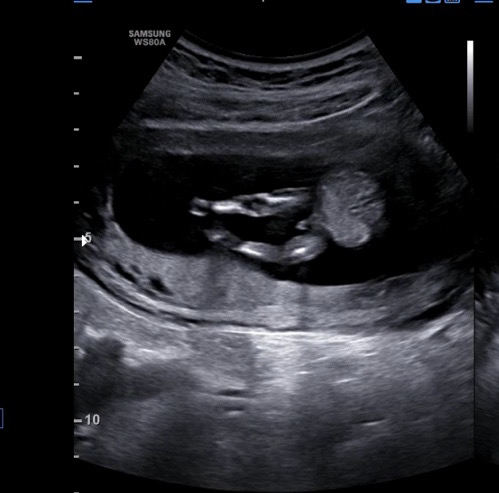

12주6일…성별은 조금 이르지만 ㅠㅠ

초음파 볼때는 몰랐는데,, 방금 영상 보다가 다리 사이에 뭐가 있어요,,, 탯줄일까요?

아들같아요!!ㅎㅎㅎ